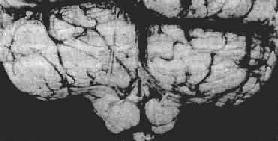

海马钩回疝

图16-7 海马钩回疝

左海马回内侧肿胀有深切迹(箭头),中脑右移变形,中脑右大脑脚受压,局部坏死出血(Kemohan切迹)